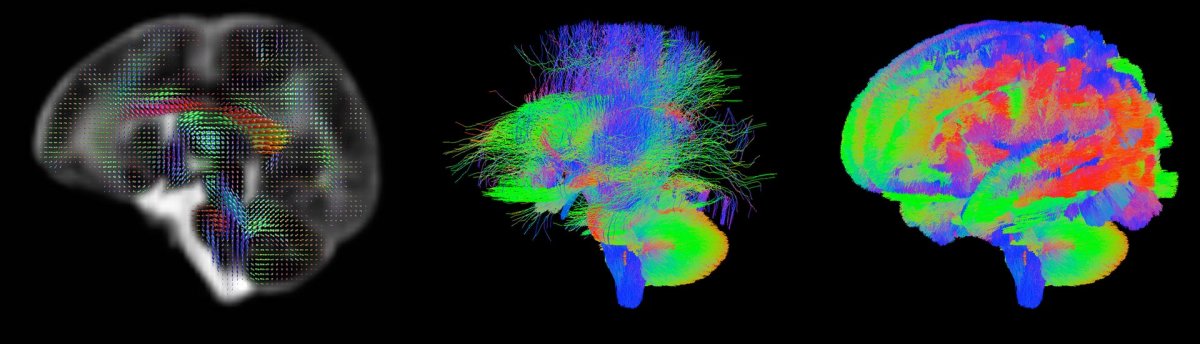

Probing the Brain’s Subtle Wiring

The project’s ultimate goal is to create the first 3D map of the gestational human brain from 20 weeks onward. They will create the map using millions of images, one taken each second, which they will then stitch together into a coherent whole. Some of the babies in the study are identified as being at a high risk of developing autism and other neurological disorders. Researchers will ideally be able to create 3D maps of high risk and average risk brains for comparison.

In the longer term, the researchers hope to have both genetic and medical data for the babies, along with their test results as they grow older. This holistic, long-term view of brain development and health outcomes would afford scientists unprecedented insights into how even the most subtle changes in the anatomy and wiring of the brain might influence health and behavior later in life, perhaps leading to new avenues of treatment for various disorders.